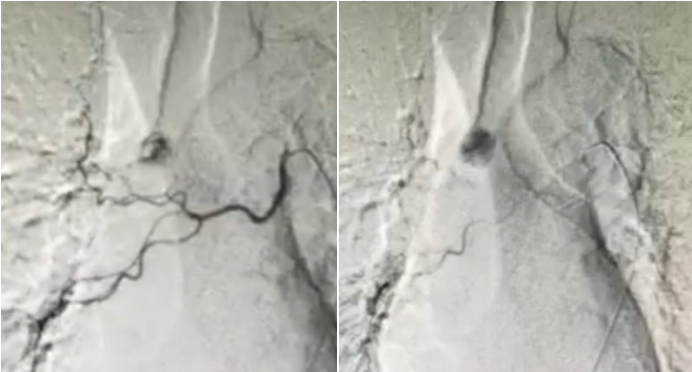

患者于放射科行支气管动脉造影,可见右主支气管有畸形血管影。该患者最终行支气管动脉栓塞术。

图片